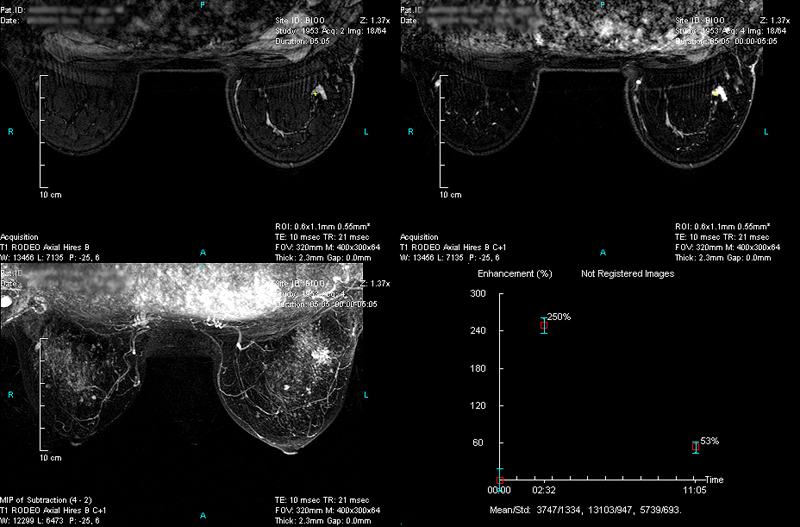

Case 1 - Left breast multi-focal cancers

(from left to right, top to down)

RODEO Pre (unspoiled), 1st Post (spoiled), MIP of Subtraction (1st Post – Pre) and TIC curve on the first lesion site.